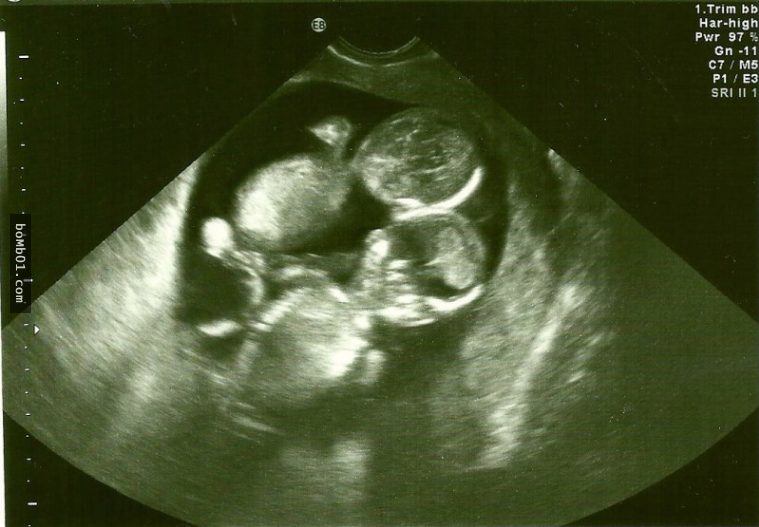

Theo một thống kê khá thú vị, cứ 100 phụ nữ thì sẽ có khoảng 5 người mang thai đôi (Ảnh minh họa)

Có nhiều nguyên nhân dẫn khiến mẹ bầu mang thai đôi (Ảnh minh họa)